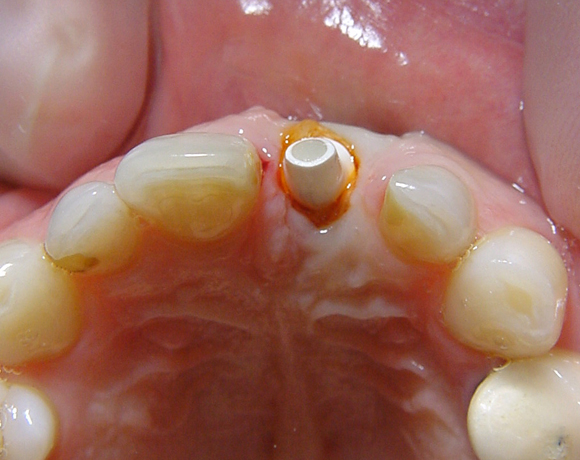

Seit 2003 ist von der Firma Thommen Medical AG ein Zirkonaufbau verfügbar, der direkt auf alle Thommen Medical Implantate verschraubt werden kann .

Vollkeramische Implantataufbauten müssen bei den meisten Implantatherstellern individuell hergestellt werden. Hier liegt ein konfektionierter Aufbau entweder in Form eines befräsbaren Zylinders oder in einer fertigen zahnstumpfförmigen Form vor.